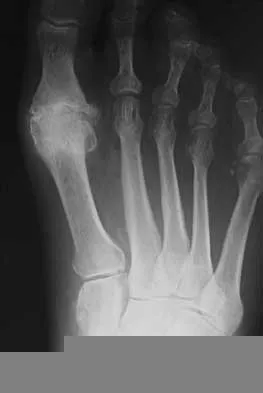

Question 332High Yield

A 6-year-old girl has the bilateral foot deformity shown in Figure 1. There is no family history of disease. Examination reveals fixed hindfoot equinus, and muscle function testing shows strong posterior tibial function, fair plus anterior tibial function, poor peroneal function, and strong gastrocnemius function. A Coleman block test shows a correctable hindfoot. Nerve conduction velocity studies show diminished function in the peroneal and ulnar nerves on both sides. Pathologic changes found in a sural nerve biopsy include "onion bulb" formation, and DNA testing confirms the presence of a mutation in the MPZ gene, consistent with hereditary motor sensory neuropathy type III (HMSN-III). What is the best course of action?

Explanation

The patient has HMSN-III or Dejerine-Sottas syndrome. This form of HMSN progresses very rapidly and frequently results in severe foot deformity in early childhood. The changes are progressive and are the result of muscle imbalance during growth. Balancing of the foot musculature is essential, particularly during the phases of rapid growth of the foot. However, this cannot be accomplished using the anterior tibial muscle because it is already weak and the transfer will further weaken it. Bony procedures also may be required, and tendon transfers cannot be depended on to correct bony deformity. However, these procedures can be deferred until the foot is closer to adult size. Surgeries that lead to joint arthrodesis, such as triple arthrodesis and some midfoot osteotomies, are contraindicated because the feet may lose protective sensation as the disease progresses. Fusions in insensate feet are less successful than realignment procedures that maintain mobility. Wetmore RS, Drennan JC: Long-term results of triple arthrodesis in Charcot-Marie-Tooth disease. J Bone Joint Surg Am 1989;71:417-422. Roper BA, Tibrewal SB: Soft tissue surgery in Charcot-Marie-Tooth. J Bone Joint Surg Br 1989;71:17-20.